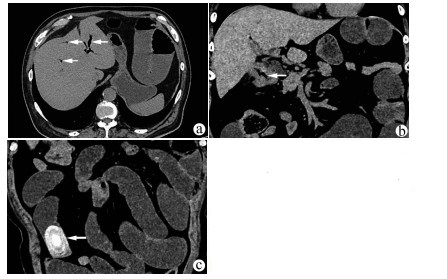

肝病超声诊断指南

中华医学会超声医学分会, 中国研究型医院学会肿瘤介入专业委员会, 国家卫生和健康委员会能力建设和继续教育中心超声医学专家委员会

2021, 37(8): 1770-1785. DOI: 10.3969/j.issn.1001-5256.2021.08.007

摘要(3138) HTML (6640) PDF (9311KB)(810)

超声检查无创、实时、价廉,无辐射、便于反复进行,是最常用的肝脏影像学检查方法。近年来,超声检查新技术如超声造影、弹性成像发展迅速,可有效鉴别肝内占位性病变性质、评估肝纤维化和门静脉高压程度以及监测肝病治疗效果,在临床肝病及其介入治疗中发挥重要诊断价值。本指南规范了肝病多模态超声技术(灰阶超声、彩色多普勒超声、超声造影、弹性超声)检查的仪器调置、患者准备及医生检查方法;对肝脏弥漫性病变(炎性病变、纤维化、硬化)、多种占位性病变及肝病介入操作的多模态超声技术诊断标准进行了定义和规范,同时推荐了超声监测周期及肝脏疾病超声诊断报告书写规范。